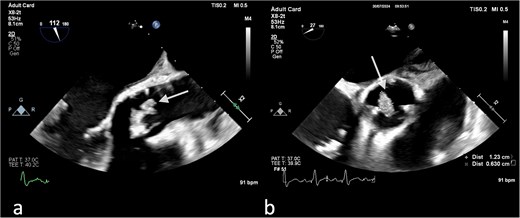

On the third day of hospitalization, transesophageal echocardiography revealed only moderate mitral regurgitation (Videos 3 and 4). However, on day 11, follow-up echocardiography showed a 7 × 18 mm vegetation on the prosthetic aortic valve, with a 5 × 7 mm floating formation (Fig. 2, Videos 5 and 6). By day 21, the vegetation had progressed, with a new formation on the tricuspid valve, an aortic annulus abscess, and worsened mitral regurgitation to severe (Figs 1 and 3, Videos 7 and 8). The development of double-sided endocarditis is very rare, and since the patient experienced it twice, congenital predisposing factors such as Patent Foramen Ovale and ventricular septal defects were ruled out. It was hypothesized that multiple predisposing factors ultimately led to the reinfection. Active IV drug use and its potential immunosuppressive effects, along with persistent poor dental condition and recurrent cutaneous infections, were identified as the main contributors, in addition to the patient’s overall non-adherence, for the development of double-sided endocarditis on two occasions.

(a) Large vegetation on the neo-right coronary cusp of the aortic prosthetic valve in TEE LAX and (b) TEE SAX (day 11 of hospitalization).